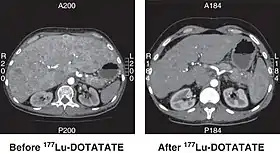

CT scan of non-functioning pancreatic NET before and 6 months after successful treatment with four cycles of 177Lu-DOTATATE.